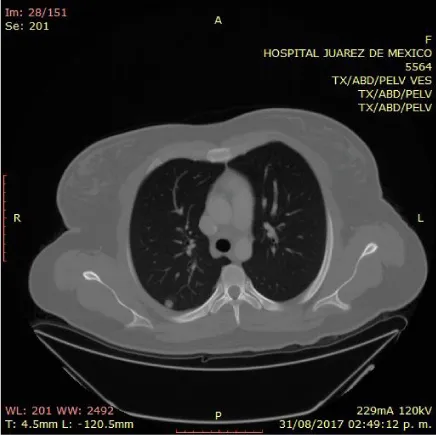

On physical examination, the patient with generalized pallor of the skin and integuments, hypotensive, tachycardic, diaphoretic, without cardiorespiratory compromise, globose abdomen due to abundant adipose panniculus, perstalsis present, pain on palpation in the right iliac fossa on bimanual touch, the uterus is delimited 8x5 cm, right annex, 12x9 cm adnexal tumor, irregular, firm, pain on cervical mobilization, with spotting-shaped transvaginal hemorrhage, extremities without edema, normal tendon reflexes. According to the clinical presentation, imaging studies, on suspicion of ruling out ectopic pregnancy, an exploratory laparotomy was performed, with findings of the right annex of 20x15 cm adhered to the uterus and sigmoid rectum without evidence of hemoperitoneum and a right salpingo-oophorectomy was performed for probable right ectopic pregnancy with hematic loss due to the surgical procedure of 40cc and sent to pathology for definitive histopathological study, during follow-up a control gonadotropin quantification was requested with the last report of 1 103 918.7 mUI/mL. The histopathological results of the macroscopic surgical specimen were right salpingo-oophorectomy, with choriocarcinoma with extensive necrosis, 1 cm tumor extension to the ovarian surface not identified, lymphovascular invasion present and free surgical margins of the residual ovarian tumor with cystic follicles, Figure 1 and the report microscopic, Figures 2-4. A new hCG quantification is performed, negative head tomography and chest tomography with probable metastasis due to pulmonary nodule, in abdomen and pelvis, presence of peritoneal carcinomatosis, with free fluid and lumbar puncture reports negative for malignant cells and chemotherapy based on cisplatin and etoposide 5 sessions and the patient is disease-free after two years of follow-up.

Choriocarcinomas, due to their great angioinvasion capacity, which facilitates their dissemination and encourages metastases to the lung, brain, liver and other organs, have early metastasis to the lung even in 80% of cases, in our case, pulmonary metastasis was diagnosed by imaging, confirming the great tumor vascular invasion; the majority die, even when diagnosed early to initiate appropriate chemotherapy, with a mortality rate of 10% to 15% [17,18]. This report describes a case that simulated an ectopic pregnancy, which underwent surgery of the administration of chemotherapy; We report that the reproductive prognosis is favorable and treatment with conservative surgery does not affect fertility. Ovarian germ cell malignancies are sometimes associated with pregnancy or term pregnancies are achieved after uncomplicated treatment with healthy term infants [19].

The tumor has a marked tendency to metastasize early by dissemination to the blood, lungs (80%), pelvis (20%), vagina (30%), liver (10%) and other rare sites gastrointestinal tract, spleen and kidney; the central nervous system is rarely involved in the absence of pulmonary metastases; but, it is one of the main causes of death. Metastases are commonly hemorrhagic due to the innate ability of trophoblastic cells to invade and erode blood vessels [26].